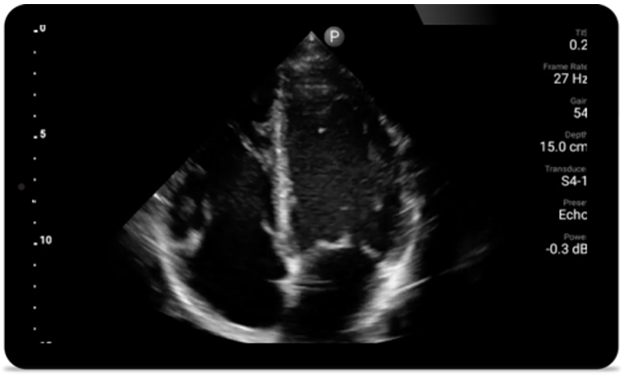

Jede Sekunde zählt in der Kardiologie

Herzinfarktpatienten benötigen unmittelbare Versorgung. Mit den kardiologischen Presets von Lumify können Patienten schneller diagnostiziert werden, um ihre Prognose zu verbessern.